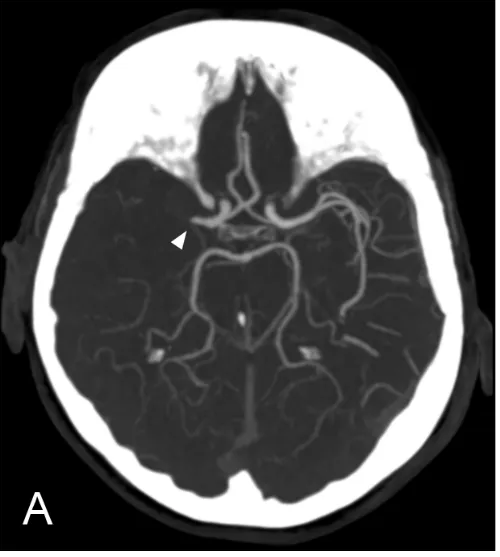

CT Angiography

CT angiography involves the injection of a contrast dye into the veins to identify clots within an intracranial blood vessel, provide insights into the stroke’s aetiology, assess the carotid and vertebral arteries in the neck, and help to guide intra-arterial thrombolysis or clot retrieval (fig. 2).

Figure 2: CT angiogram of a patient with a stroke. The arrow shows a blockage in the blood vessel, where the contrast (and therefore also blood) cannot pass.